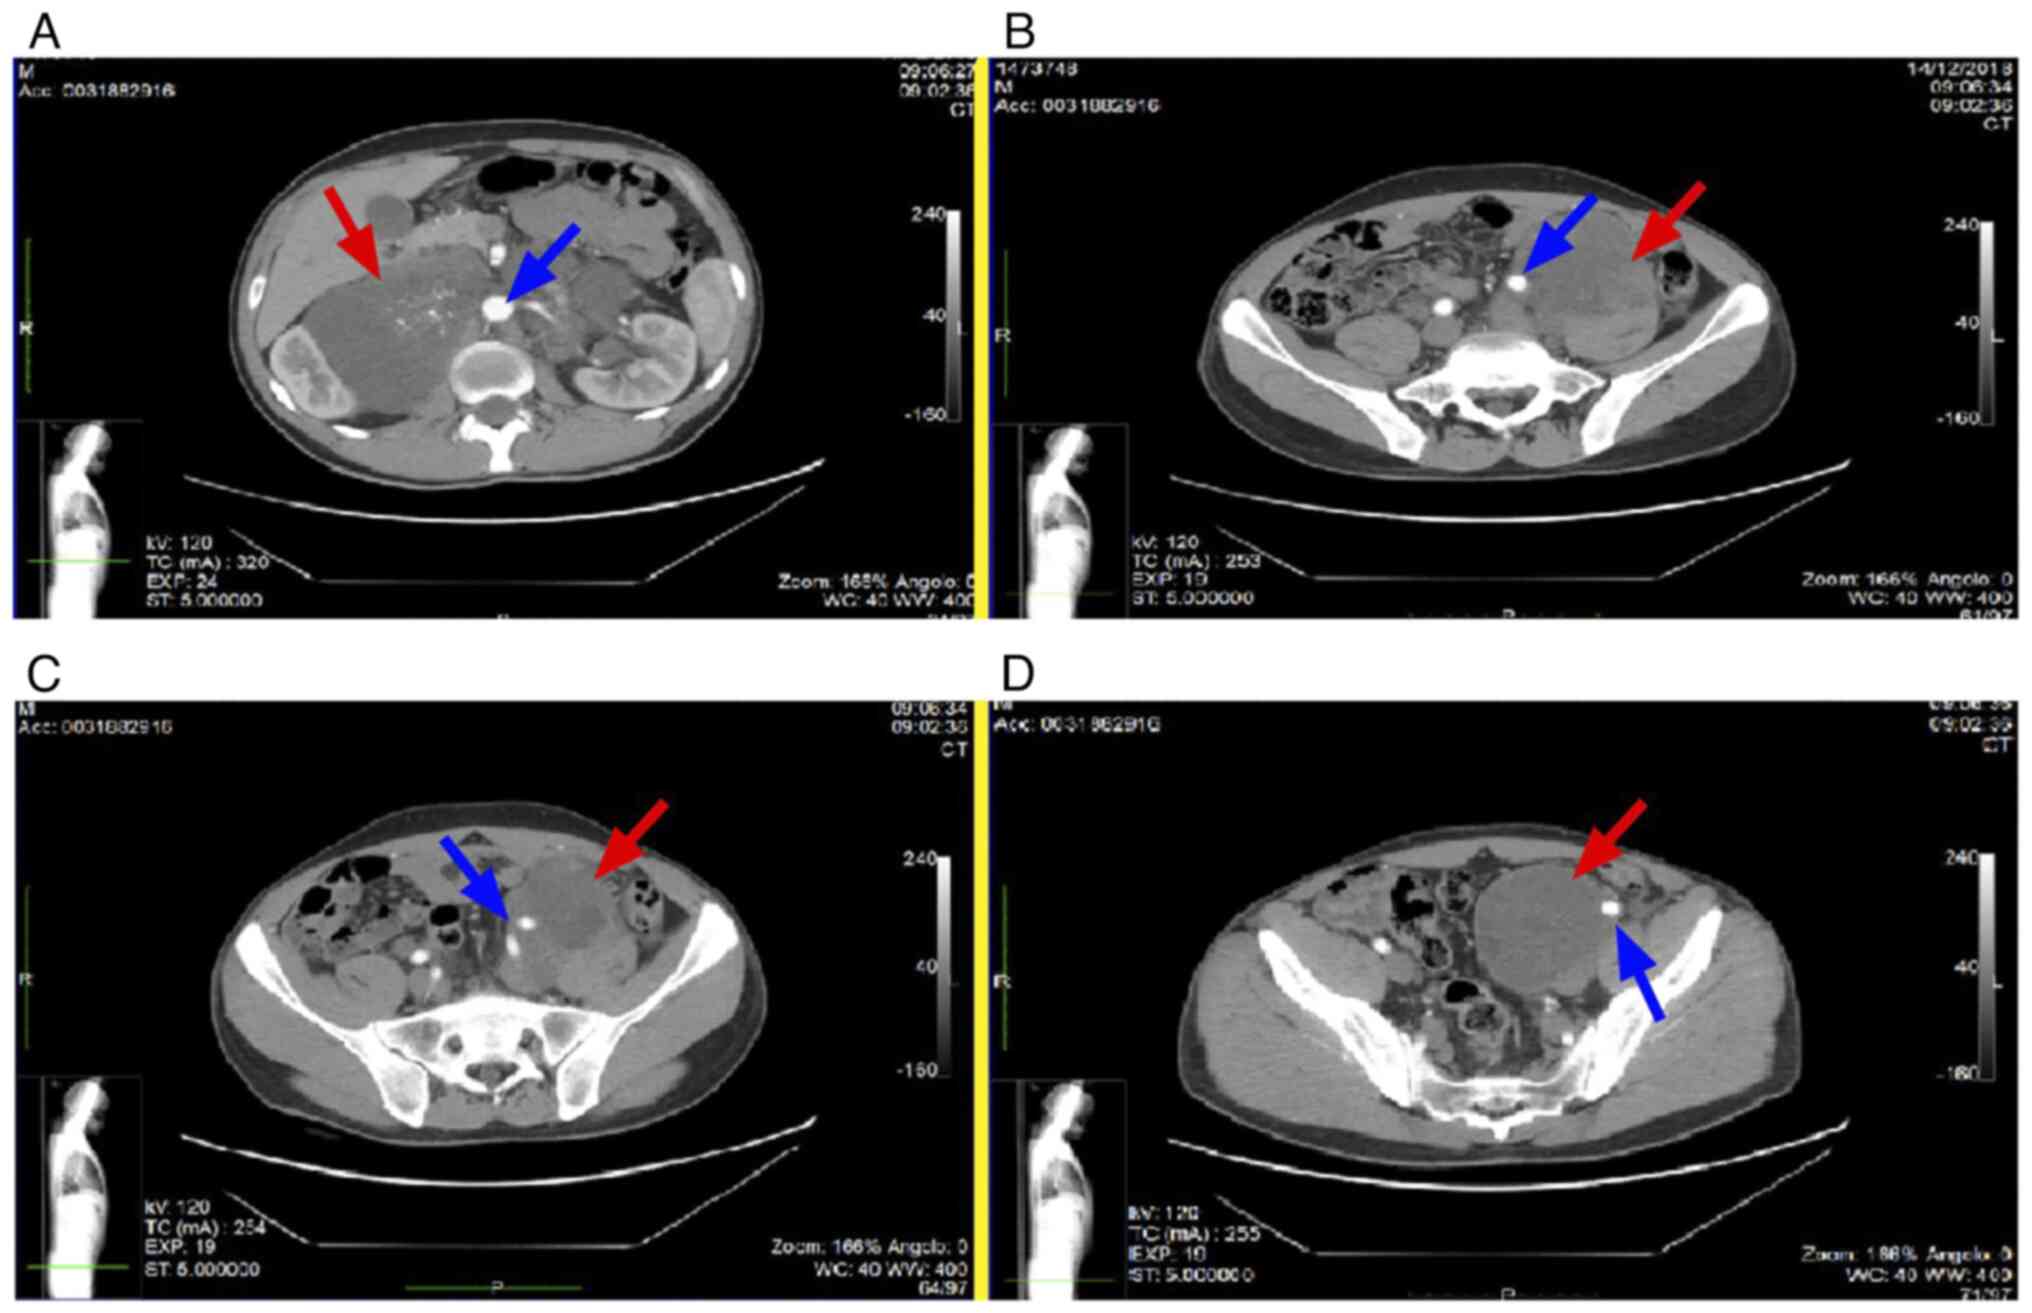

A 29-year-old male was admitted to the Internal Medicine Unit of another hospital due to symptoms of incomplete ileus (diffuse abdominal discomfort, nausea and abdominal distension), associated with fever and loss of appetite; the patient had no relevant past medical history, without common risk factors for testicular cancer (such as the presence of tumor in the contralateral testis, history of cryptorchidism or undescended testis, hypotrophic testis and Klinefelter syndrome). Furthermore, no family history of testicular cancer was reported among first degree relatives. A Computed Tomography (CT) scan revealed the presence of lymphadenopathies affecting the neck, mediastinum and retroperitoneum. In particular, the lymphadenopathies of the retroperitoneum and of the left external iliac site were voluminous, forming packages up to 18 cm in diameter, with infiltration of the large retroperitoneal vessels (Fig. 1A), the left common iliac vessel (Fig. 1B) and the left external iliac vessel (Fig. 1C and D).

Figure 1

Pre-operative evaluation of the patient with imaging techniques. This CT, also performed with contrast medium, showed the lymphadenopathies of the retroperitoneum. (A) Arterial phase of the CT scan in which the voluminous lymph node mass is indicated by the red arrow while the blue arrow indicates the aorta. (B) The blue arrow shows the left common iliac artery while the red arrow indicates lymphadenopathy. (C) The blue arrow indicates the bifurcation of the left iliac arterial axis in the left internal and external iliac artery while the red arrow indicates the lymph node mass. (D) Voluminous lymphadenopathy (indicated by the red arrow) incorporates the left external iliac artery (indicated by the blue arrow).